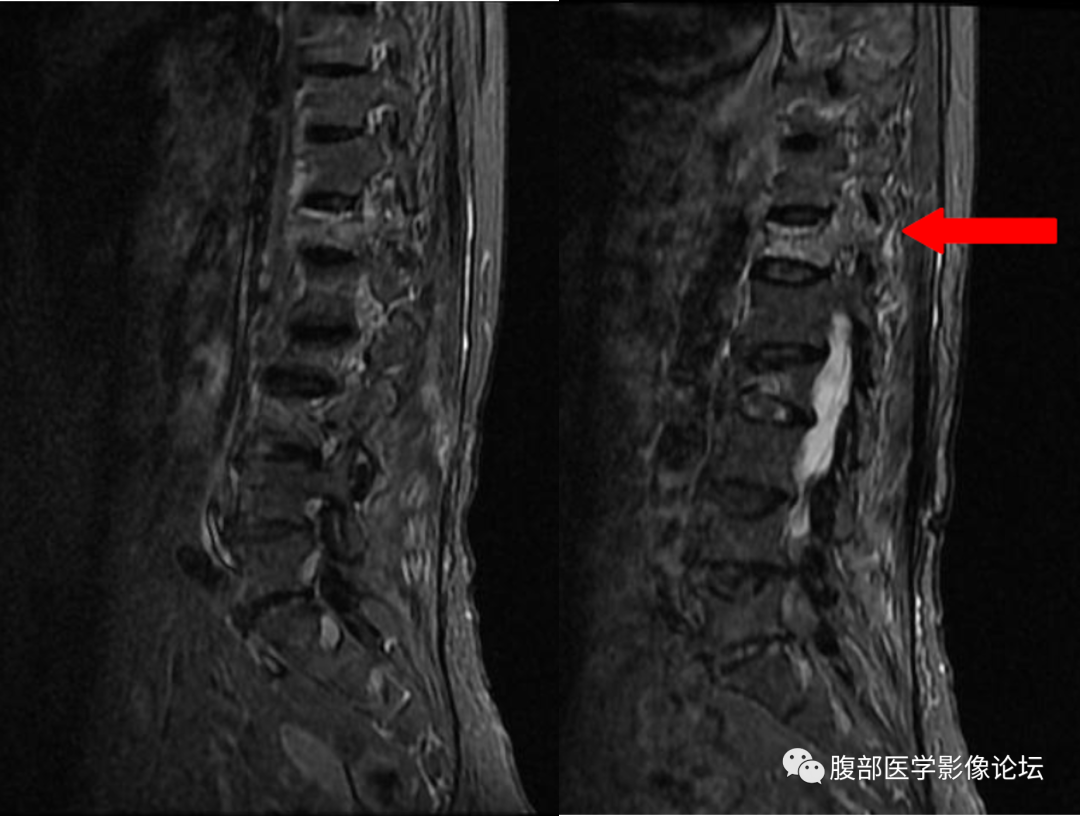

6、椎旁软组织改变

良性骨折:椎旁软组织轻度肿胀

恶性骨折:椎旁软组织肿块

椎体良性与恶性骨折的鉴别其实还有一些鉴别点,但是笔者认为上面六点是最主要的,同时需要指出,任何单独一个鉴别点都不是绝对的,就拿本例来说,仔细看,T1WI 系列还是可以看到一小部分黄骨髓的,但是椎弓根有受累,又是老年人,我们要想到转移瘤的可能,所以我们要仔细阅片,避免不必要的医疗纠纷。